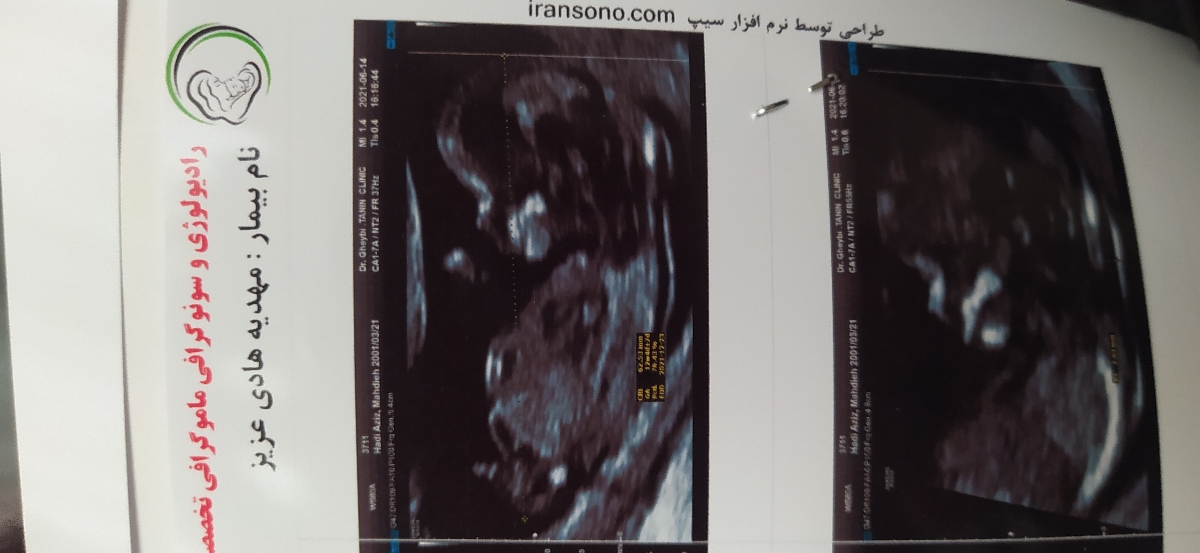

خانما من سونو گرافی ntدادم بنظرتون جنسیتش چیه خیلی ذوق دارم زود بفهمم

عکس سونوتو اگ داری بفرس

مهدیه هادی عزیز

پسر

پسره احتمال زیاد

پسرررره

پسره

سرش مثل برا من مربعی هست

دکتر سونو کردنی با اطمینان کامل نمیگه

حدس میزنن فقط